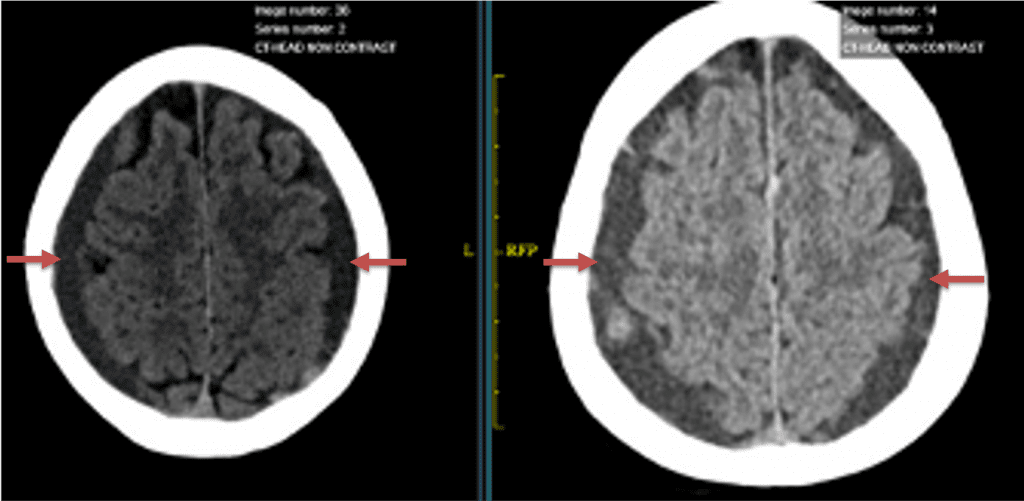

The patient agreed to receive minimally invasive treatment with Bilateral Middle Meningeal Artery Embolization, a new approach to promote resorption of chronic and subacute subdural hematomas in patients that are not improving with conservative measures or have contra-indications to surgical evacuation. Selective catheterization of the Middle Meningeal Artery is followed by transarterial embolization of the territory and inflammatory membranes that are felt to be secreting serosanguinous proteinaceous exceeding the capacity for resorption. MMA embolization was performed bilaterally in this patient. (Figure 2. A and B)

Figure 2. A) Initial right ECA angiogram ; B) Post MMA Embolization; C) Selective Embolization Of Middle Meningeal Artery Membranes using PVA particles (arrows).